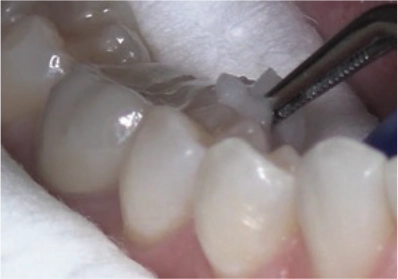

Use cotton pliers/hemostat to pick up the soft saturated sponge.

Apply for approx. 5 seconds

For interproximal application, apply from the lingual embrasure followed by the buccal embrasure.

The non-invasive therapy with CURODONTTM REPAIR FLUORIDE PLUS (CRFP) is as safe as its application is easy. The entire process of applying CRFP is completed within 8-10 minutes, without drilling, anesthesia, or pain.